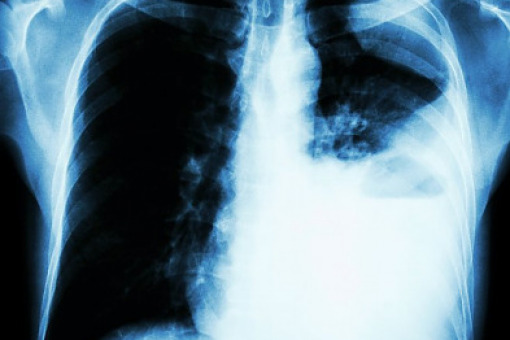

Podsumowanie roku w raku płuca

Prof. Chorostowska-Wynimko o raku płuca – podsumowanie 2024 r. w pneumonologii ►